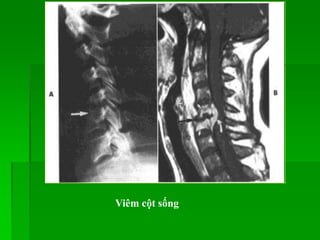

NHIỄM TRÙNG

 Viêm cột sống > viêm đĩa đệm > áp xe ngoài màng cứng >> áp xe tủy.

 Nguyên nhân thường gặp nhất: S.aureus, tỉ lệ tăng ở người nghiện,

suy giảm miễn dịch, có thể do lao…

 Vị trí: từ đĩa đệm  thân sống (trẻ em); từ thân sống (vùng dưới sụn)

đĩa đệm (người lớn).

 Hình ảnh:

- XQ: bình thường ở giai đoạn sớm

- MRI: Đĩa đệm, thân sống tăng tín hiệu trên T2W, TIRM, bắt

Gd sau tiêm.Thường kèm khối mô mềm, áp xe ngoài màng cứng, viêm

màng tủy. TH do lao đôi khi đĩa đệm không bị tổn thương.

Viêm cột sống và đĩa đệm do vi trùng thường và do lao:

Viêm thân sống-đĩa đệm L14

Spondylodiskitis

Viêm cột sống